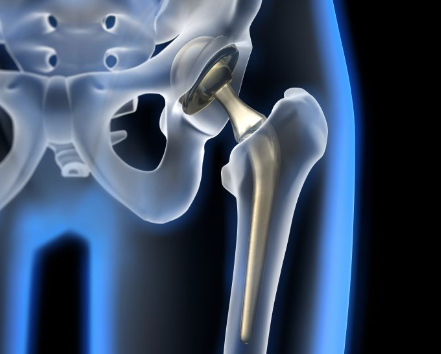

고관절 치환술(Total Hip Arthroplasty)

적응증: 고관절 치환술은 고관절 골관절염, 류마티스 관절염, 무혈성 괴사 또는 고관절 골절이 있는 개인에게 일반적으로 수행됩니다.

절차: 고관절 치환술 중 손상된 고관절의 볼-소켓 구성 요소를 인공 부품으로 교체합니다. 이 절차는 다양한 수술적 접근법을 사용하여 수행될 수 있습니다.

혜택: 고관절 치환술은 통증을 완화하고 고관절 기능을 회복하며 환자가 독립성과 이동성을 회복할 수 있도록 해줍니다.